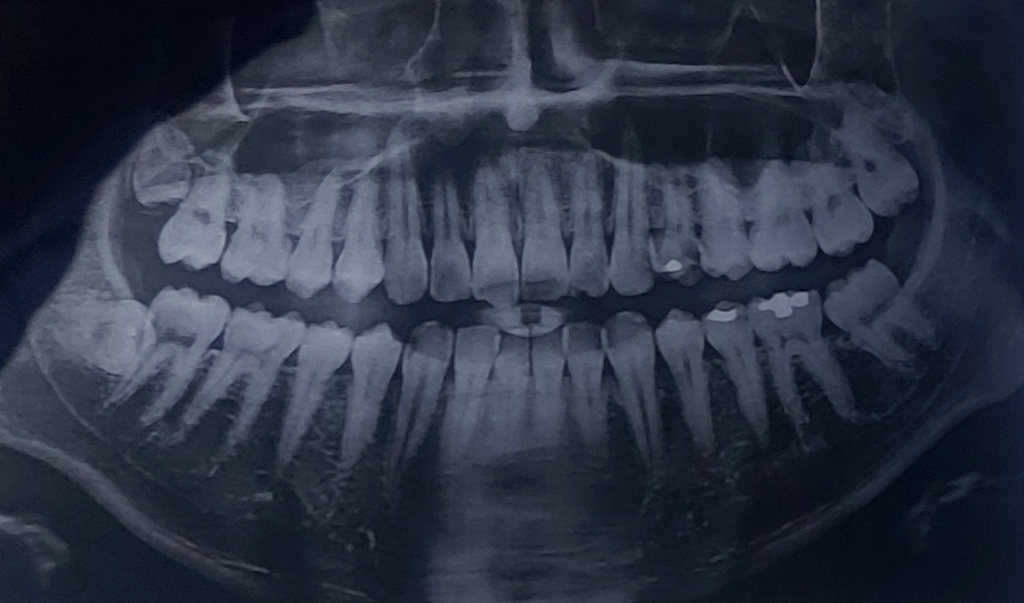

차가운거 먹었을 때 이가 시린 증상이 있어서 오늘 치과에 가서 검진을 받았습니다

육안으로 보이는 충치는 없어서 바람 쏘면서 시린지 물어보셨고 시리지 않다고 하니 아이스막대로 확인해보셨습니다. 시린 증상 있는 이가 총 두 개 였구요 그 두 개만 집중적으로 사진 찍어서 보여주셨습니다

사진 보시자마자 두 개 다 신경치료해야한다고 하시던데 제가 일단 검진만 계획하고 와서 다음에 다시 오겠다하니

• 3번 째 사진

사진상으로는 신경치료를 해야될 가능성이 높습니다만

엑스레이 상으로 봐도 충치가 깊어 보입니다. 신경치료를 해야될 가능성이 높아 보이네요.